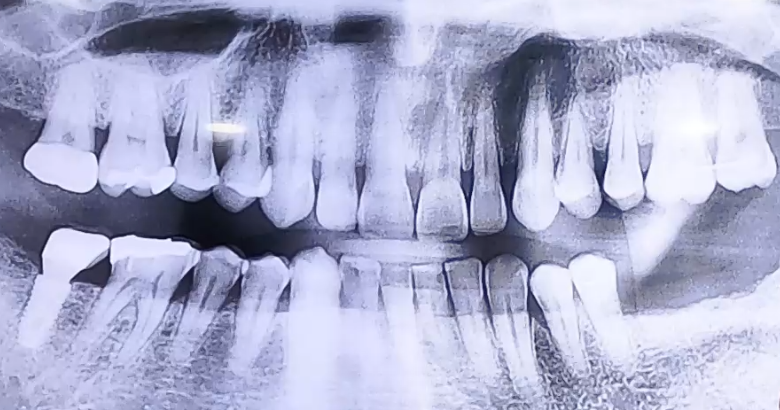

AFTER

잇몸뼈 상태는 양호하였고 임플란트도 머리 부분만 파절되었기 때문에

임플란트 보철을 분리하고 머리 부분만 새로 제작해 드렸습니다.